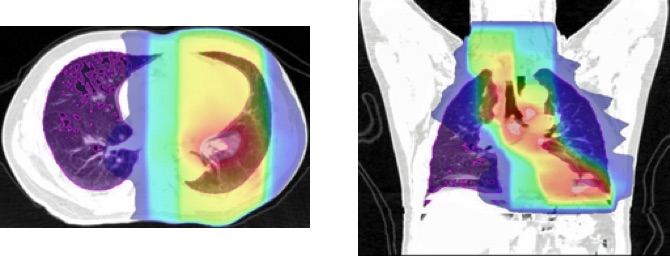

放射線療法をうける肺癌患者さんで、放射線肺臓炎が起こる危険因子についての検討を行っています。